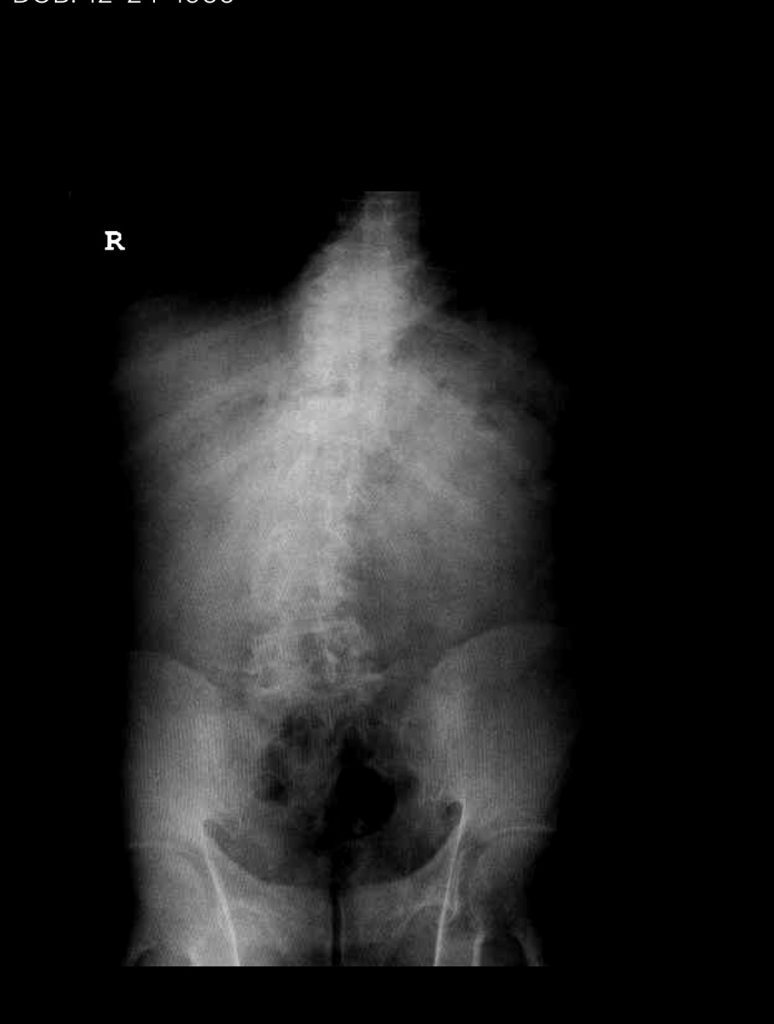

Figure 1. AP lumbar x-ray demonstrating degenerative lumbar levoscoliosis with secondary arthritic changes.

He had mild proximal weakness of his hip flexors. He also had a history of diabetes, hypertension, and hypercholesterolemia. Imaging studies were obtained. Plain x-rays (Fig. 1) demonstrated a degenerative levoscoliosis with the apex of the curve at L2-3. Lumbar MRI (Fig. 2) showed severe degenerative disc disease with an L5-S1 grade 1 spondylolisthesis and a significant retrolisthesis at L3-4 with severe lumbar stenosis.